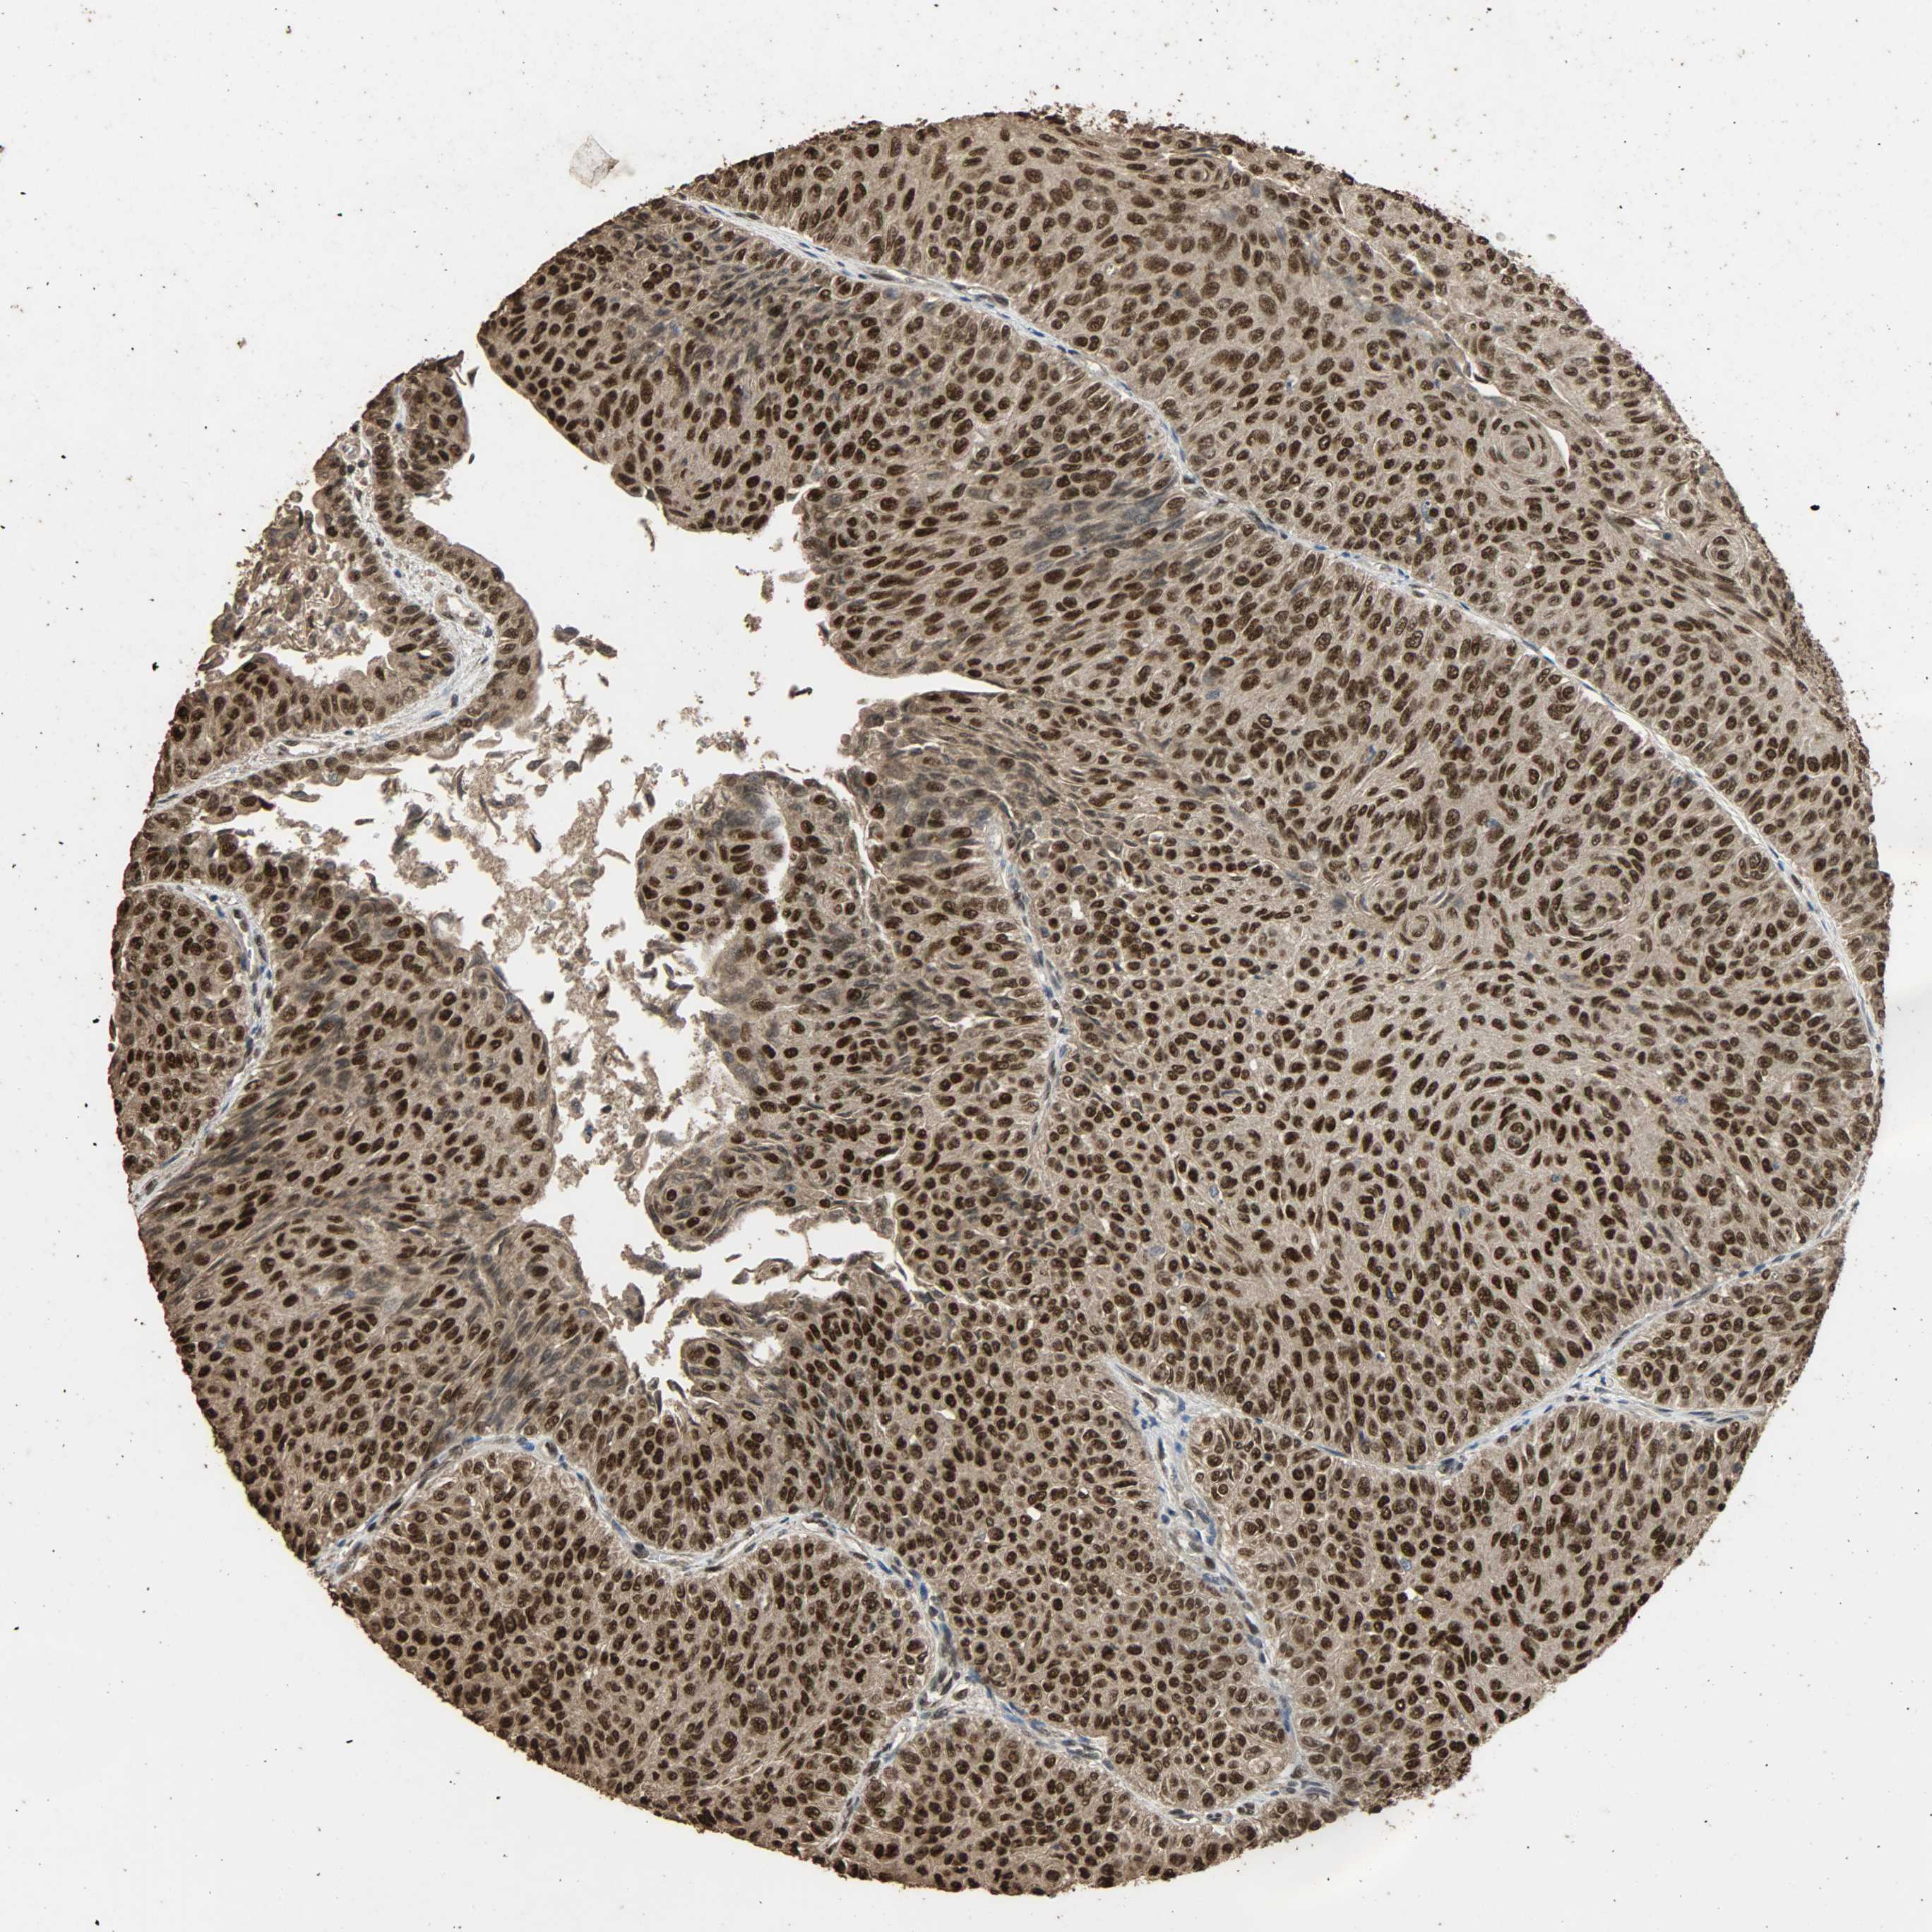

UROTHELIAL CANCER - Protein expressioni

A mouse-over function shows sample information and annotation data. Click on an image to view it in a full screen mode. Samples can be filtered based on level of antibody staining by selecting one or several of the following categories: high, medium, low and not detected. The assay and annotation is described here.

Note that samples used for immunohistochemistry by the Human Protein Atlas do not correspond to samples in the TCGA dataset.

Antibody stainingi

Antibody staining in the annotated cell types in the current human tissue is reported as not detected, low, medium, or high, based on conventional immunohistochemistry profiling in selected tissues. This score is based on the combination of the staining intensity and fraction of stained cells.

Each image is clickable and will lead to virtual microscopy that enables deeper exploration of all samples and also displays staining intensity scores, fraction scores and subcellular localization as well as patient and tissue information for each sample.

Antibody HPA005559

Staining

High

Medium

Low

Not detected

Intensity

Strong

Moderate

Weak

Negative

Quantity

>75%

75%-25%

<25%

None

Location

Nuclear

Cytoplasmic/membranous

Cytoplasmic/membranous,nuclear

Urothelial carcinoma, High grade

Urothelial carcinoma, Low grade